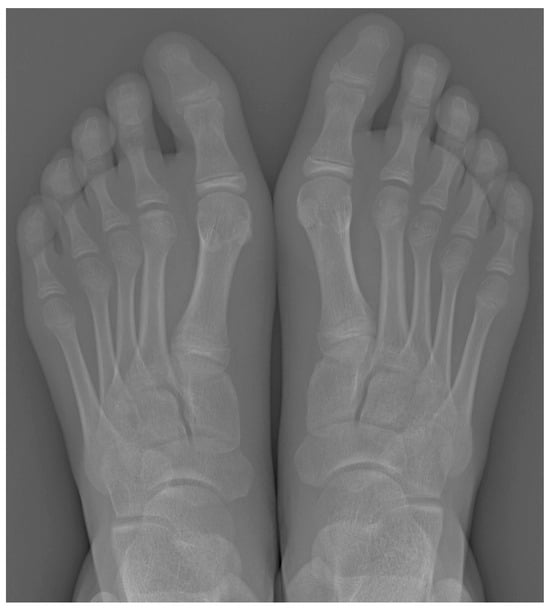

Plain radiographs are the cornerstone of imaging in the diagnosis of lesser metatarsal osteochondrosis. In the early stages of the disease, when supported by a suggestive clinical presentation, obtaining a comparative radiograph of the contralateral foot can be a useful diagnostic tool (Figure 9).

Figure 9.

Radiograph of a symptomatic 10-year-old female patient showing early sclerosis and flattening of the second metatarsal head on the left foot, compared to the contralateral side.

In the later stages, radiographs may reveal characteristic changes including subchondral sclerosis, fragmentation, and flattening of the affected metatarsal head (Figure 10 and Figure 11). In some cases, the presence of joint space narrowing or bony irregularities may also be observed. However, early changes, such as bone marrow edema or subtle cartilage damage, may not be visible on standard radiographs. MRI is particularly useful in the early stages of the disease, as it can detect bone marrow edema, which is a sign of active bone inflammation and necrosis, even before structural changes become apparent on radiographs (Figure 10, Figure 11 and Figure 12).